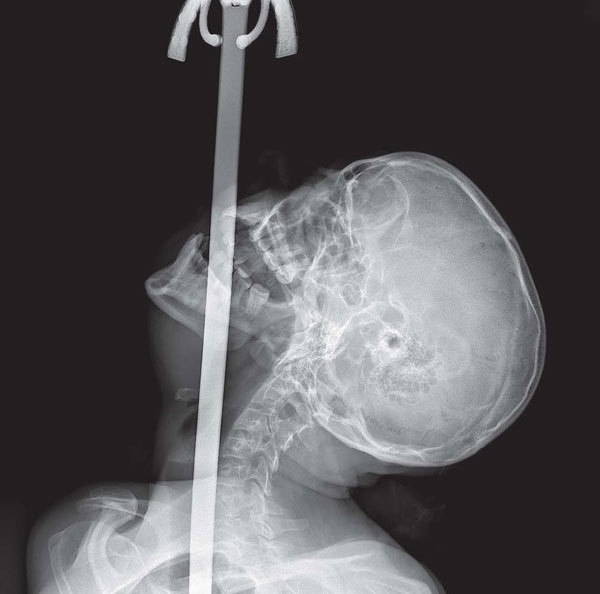

Однажды на скучной лекции по анатомии горла профессор сказал: «Если что-то застревает в горле, можно открыть проход, выдвинув нижнюю челюсть». Чтобы проиллюстрировать свои слова, он показал рентген шпагоглотателя в момент глотания шпаги.

Иллюстрация к книге — Фактологичность. Десять причин наших заблуждений о мире – и почему все не так плохо, как кажется [i_001.jpg]